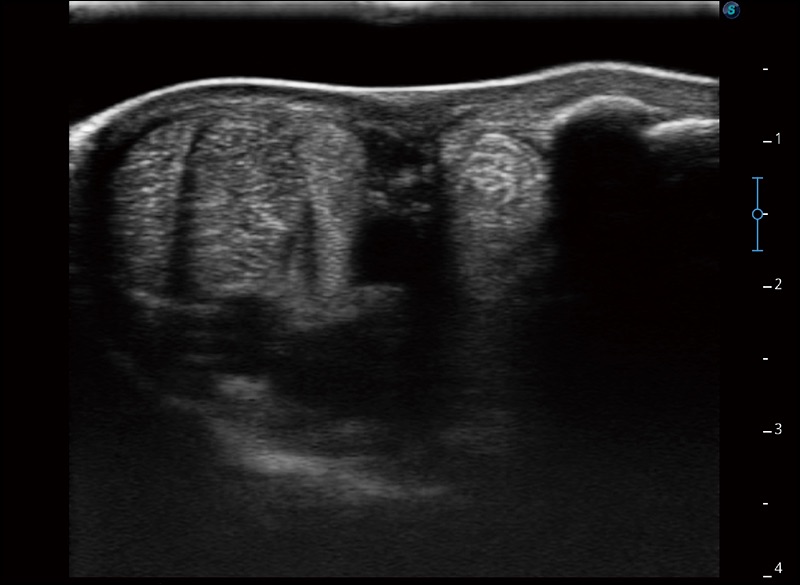

穿刺针增强

高清显示穿刺进针情况

连续波多普勒成像CW

为心脏功能评估提供更多诊断信息